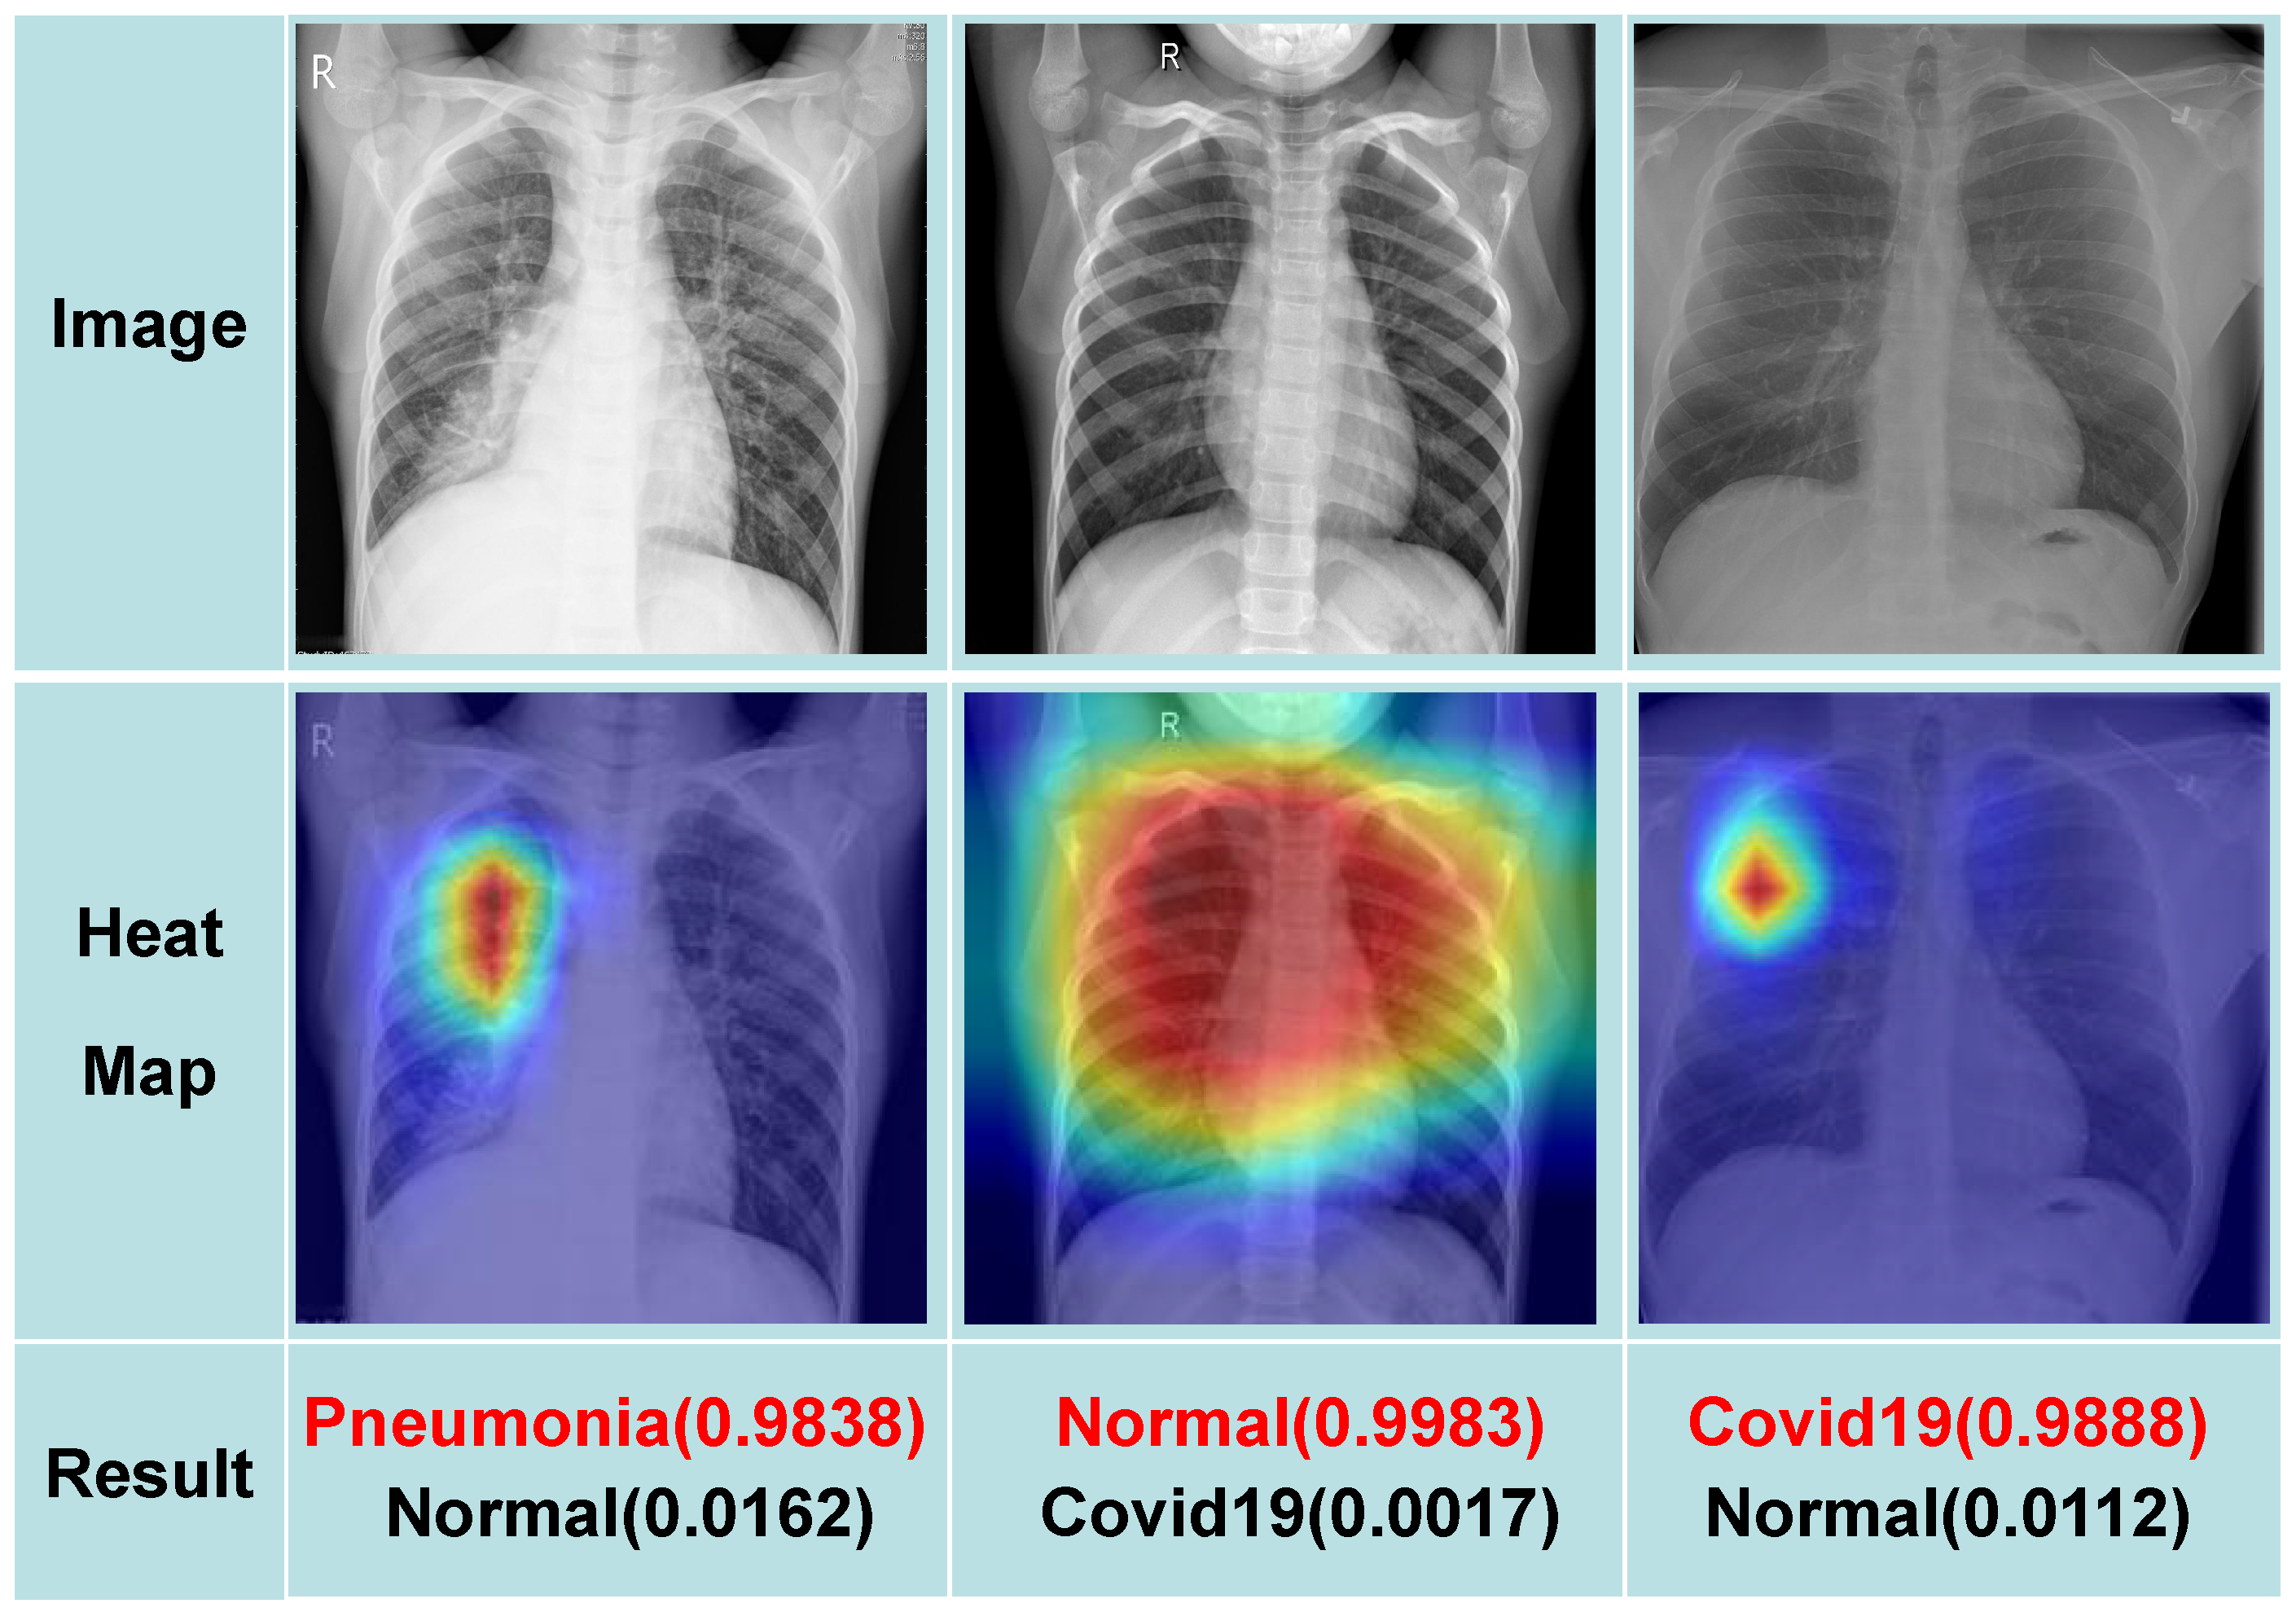

Ensuring the network’s proficiency in assimilating feature information from medical images is crucial for enhancing model interpretability. The utilization of the Grad-CAM [51] technique serves to generate a heat map of the chest X-ray image, enabling the visualization of the specific regions of focus for the model. Figure 8 showcases the classification results based on the fused images, underscoring the practical viability of our proposed methodology. This approach holds promise for practical implementation and proves pivotal in addressing noise interference challenges in chest X-ray image classification, ultimately enhancing overall model performance. In our model, the final decision is determined by the highlighted region in Figure 8. The model identifies high-attention areas in a heat map that exhibit significant overlap with critical anatomical structures (e.g., pulmonary consolidation zones, pleural adhesion regions). These high-attention regions strongly correlate with key pathological features, substantially enhancing the interpretability of model predictions. For medical professionals, these highlighted areas in the image along with the predicted outcomes serve as valuable aids in disease diagnosis.

Figure 8. Fused image classification results show practical viability and enhanced model performance, with additional insights from the Grad-CAM generated heatmap.